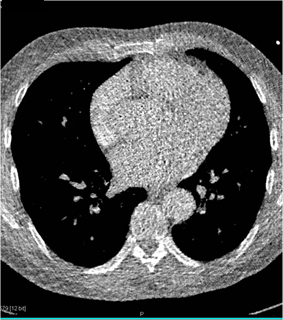

On this cardiac CTA why do the images seem of such poor quality?

the image was reconstructed from data outside the selected prospective rendering window (60-75%)

the patient had a PVC